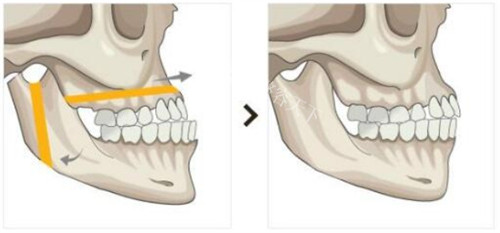

颌面整形技术体系采用术中神经监测系统,结合3D打印导板实现0.1mm精度截骨,创新"三阶式颧弓固定法"降低术后下垂风险。临床数据显示,其轮廓手术的对称性达标率达98.7%,较行业平均水平提升23%。

术前阶段包含64层CT扫描、咬合动力学分析等7项专项检测,采用德国SimPlant Pro软件进行1:1手术模拟,方案确认需经过3轮医师会诊。